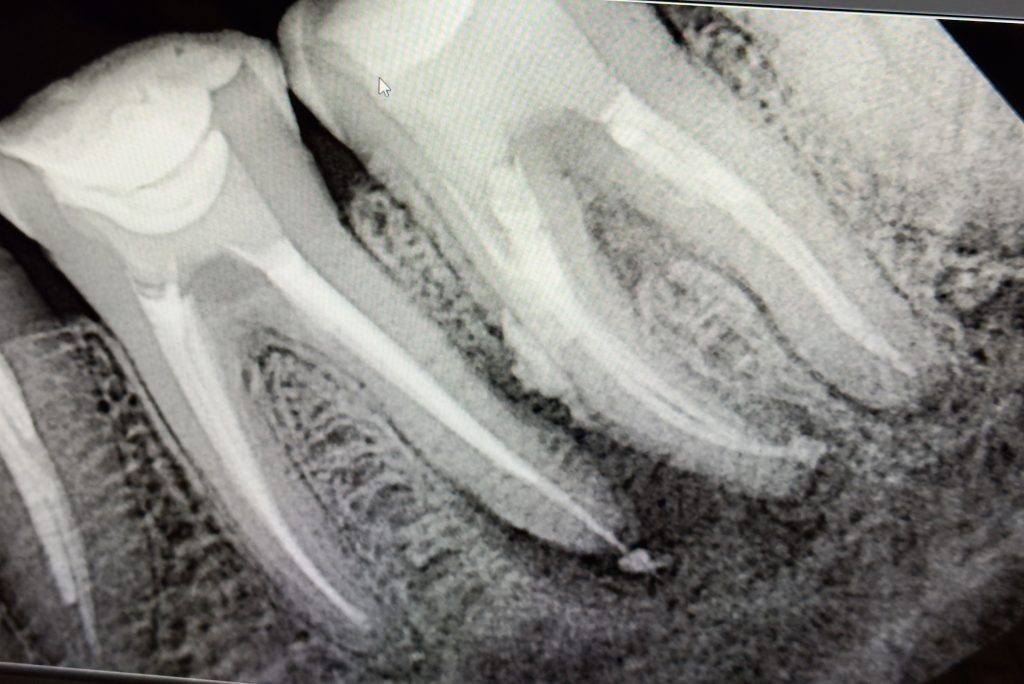

1️⃣ Pre-Operative Assessment

The patient presented with deep caries and pain in the upper right quadrant involving tooth #6 and #7 (Fig 1). Pulp testing confirmed irreversible pulpitis in #6 and necrosis in #7. Radiograph showed extensive coronal destruction and periapical widening.